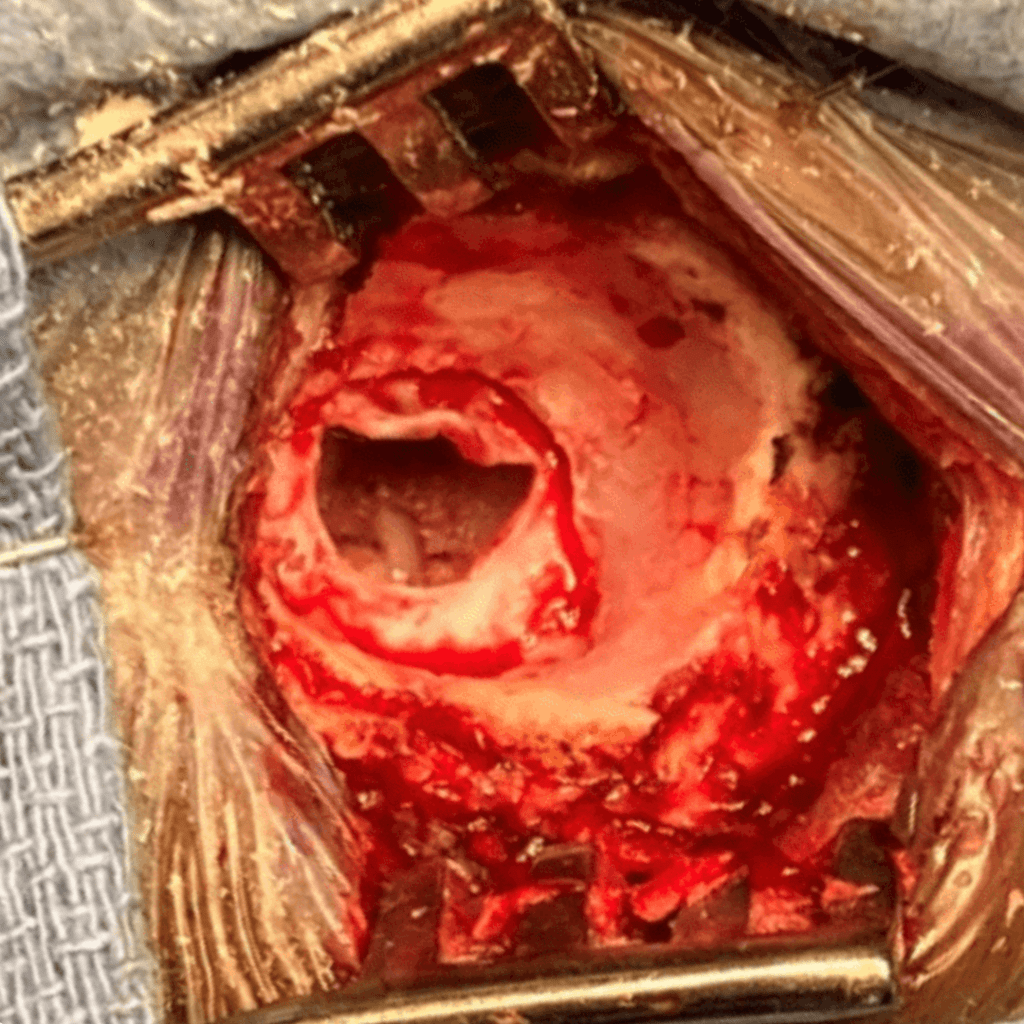

In this case, a loop of the superior cerebellar artery was causing significant compression and distortion of the trigeminal nerve root (Figure 3). The superior cerebellar artery is the usual offending blood vessel in cases of trigeminal neuralgia. Using micro-dissection techniques with appropriate micro -instruments, the artery is dissected off the nerve, and very small pieces of teflon felt (a non-absorbable material) are used to keep the artery from recompressing the nerve. The final image under the microscope shows the trigeminal nerve root fully decompressed, with resumption of normal anatomy (Figure 4).